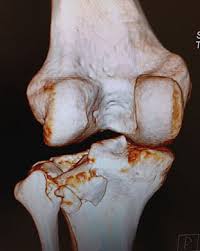

A Complexidade Do Quadrante Postero Lateral Nas Fraturas Do Planalto Tibial Relato De Um Caso Atipico E Revisao Da Literatura Relatos De Casos Do Cbc Revista Do Colegio Brasileiro De Cirurgioes

Fratura De Plato Tibial Ou Fratura De Tibia Proximal Dr Denys Aragao